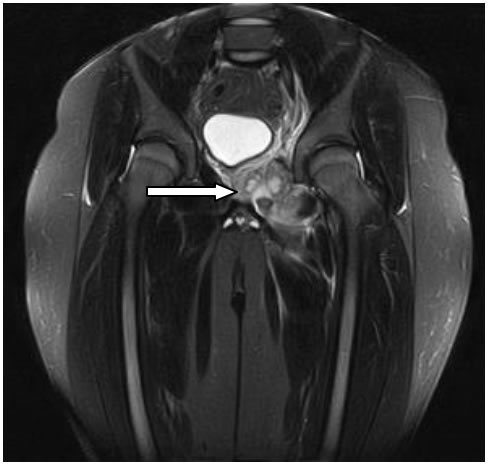

Decidiamo di eseguire la RMN del bacino. (Figura

1)

Tale indagine ci permette di evidenziare una localizzazione

ascessuale a carico dei muscoli otturatore interno ed esterno di sx

consensuale ad un quadro di osteomielite della branca ischio-pubica

di sx. Alla luce di tali evidenze ripetiamo, poi, una radiografia del

bacino (a distanza di circa 2 settimane dall'esordio della

sintomatologia) che effettivamente dimostra il rimaneggiamento

osteo-strutturale della branca ischio-pubica di sx. confermando,

pertanto, il limite “temporale” di tale metodica. (Figura

2)

Figura

1.

RMN: estesa alterazione di segnale coinvolgente la branca

ischio-pubica sx ed i muscoli otturatori omolaterali. La branca

ischiopubica mostra un'architettura spongiosa irregolare con

interruzione corticale sul margine anteriore; i gruppi muscolari

appaiono aumentati di volume e caratterizzati da segnale interno

disomogeneo con componenti liquide settate da riferire a raccolte

ascessuali.